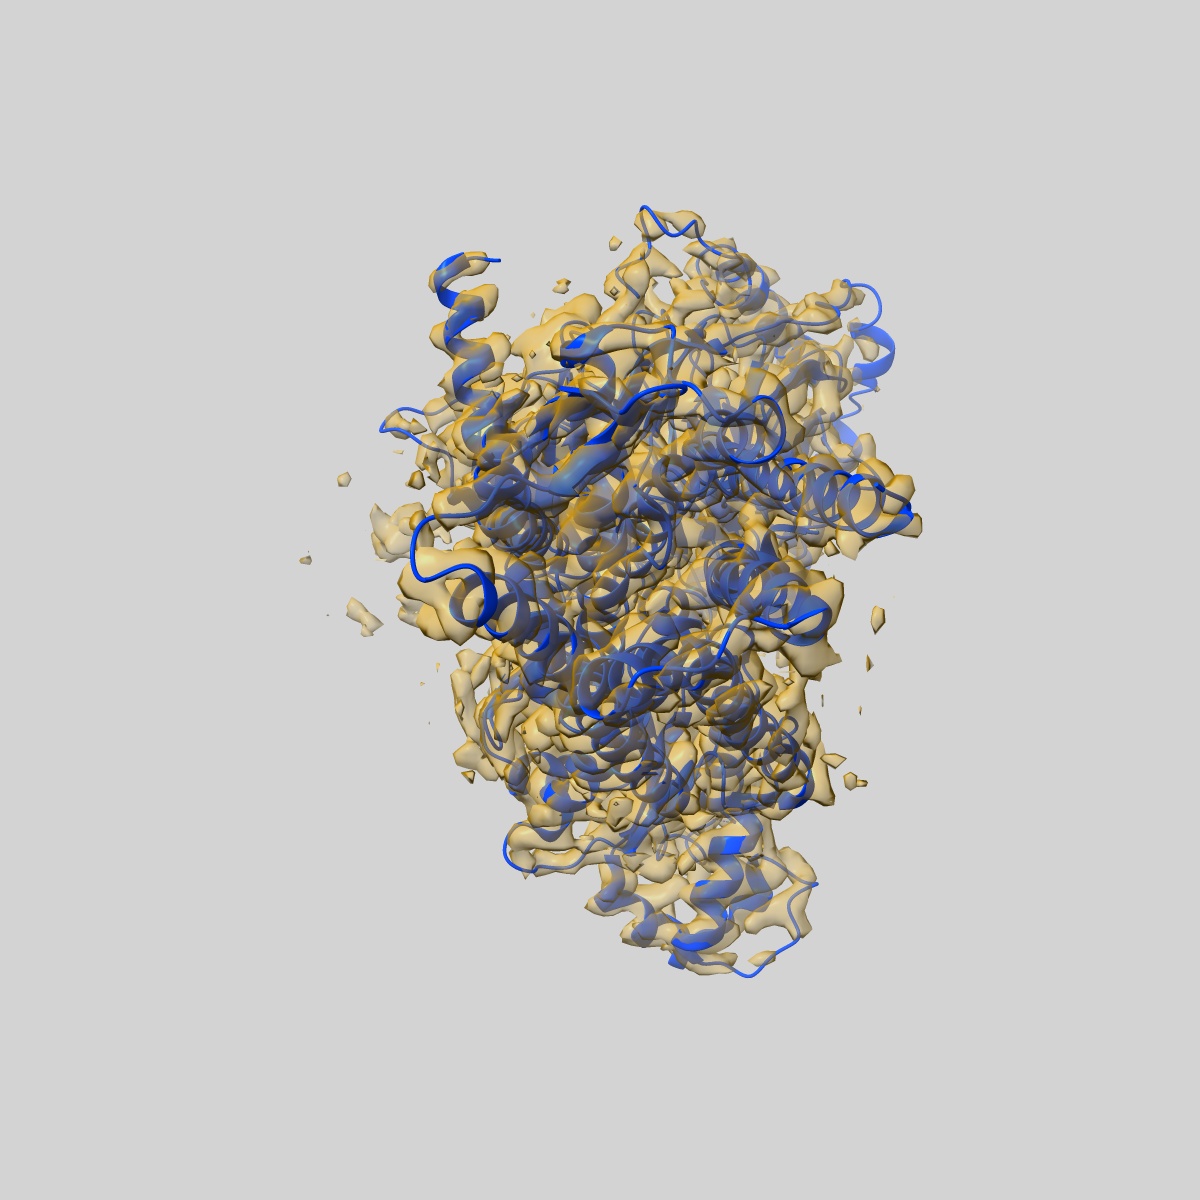

DAMGO-bound mu-opioid receptor-Gi complex

Single-particle3.3 Å

Sample: fentanyl bound mu-opioid receptor-G protein complex

Fitted models: 8efq

Molecular recognition of morphine and fentanyl by the human mu-opioid receptor.

(2022) Cell , 185 , 4361 - 4375.e19